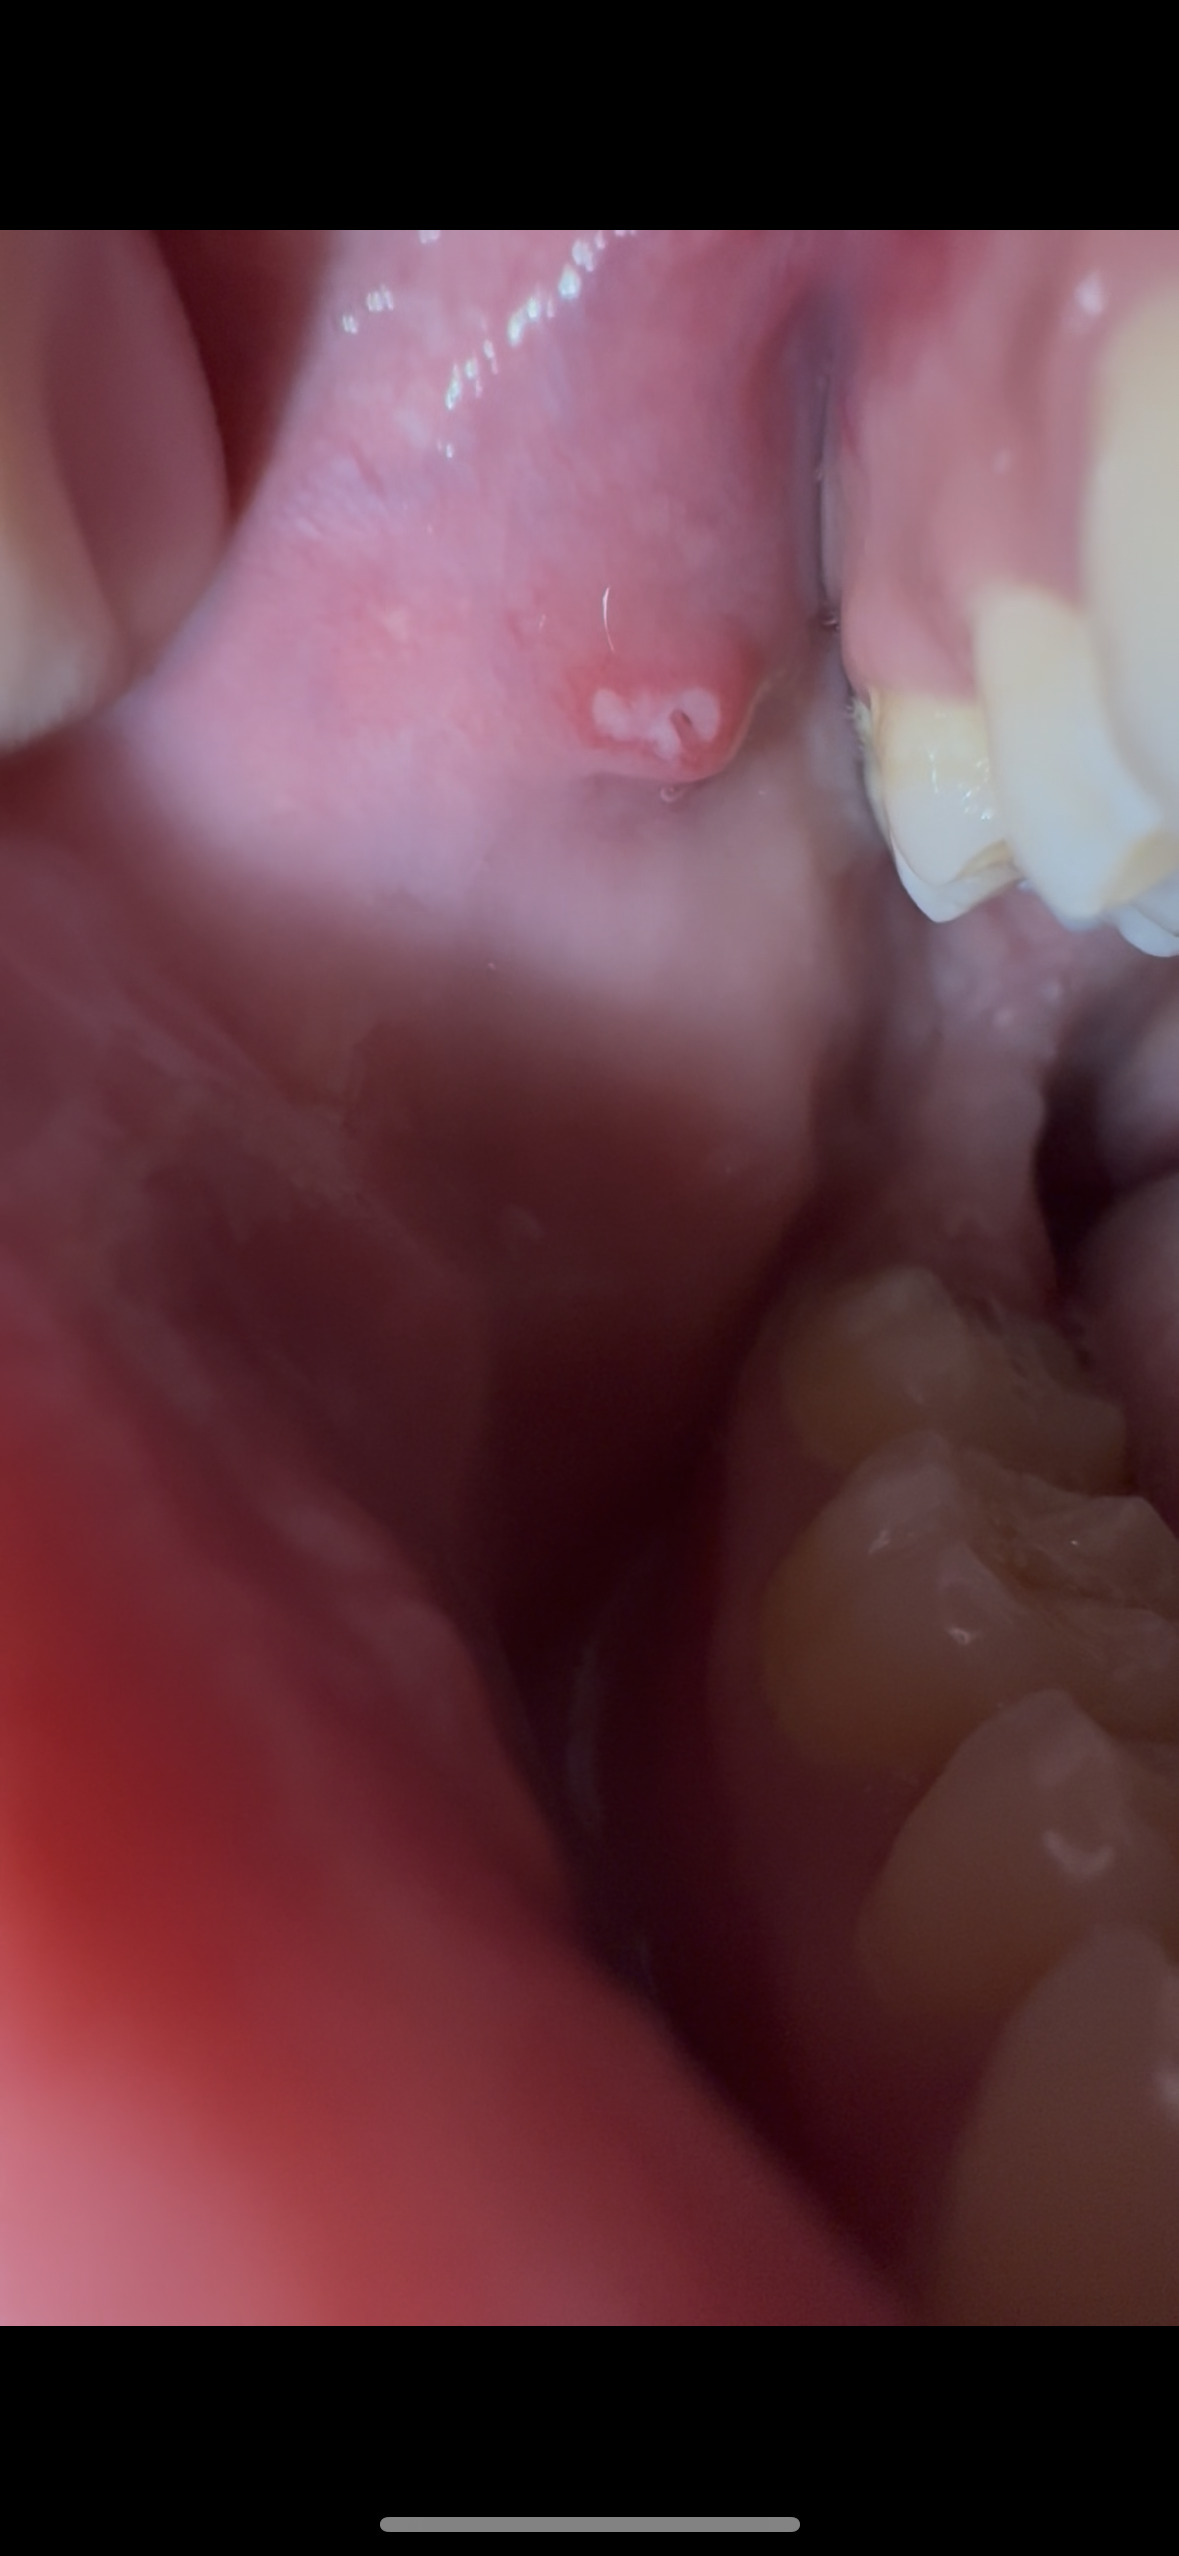

[写真あり] 1週間前から右上6番の頬の内側が腫れています

歯茎(歯ぐき)の腫れ 粘膜の病気・異常 その他(写真あり) 口内炎 |